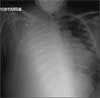

A chest radiograph revealed complete opacification of the right lobe and partial opacification with infiltrate of the left lung, suggestive of acute pneumonia. Metastasis of the testicular cancer to the lungs was suspected. The patient was transferred to a tertiary care center for further evaluation and treatment by an oncologist. Further testing, including thoracentesis, confirmed the metastasis.